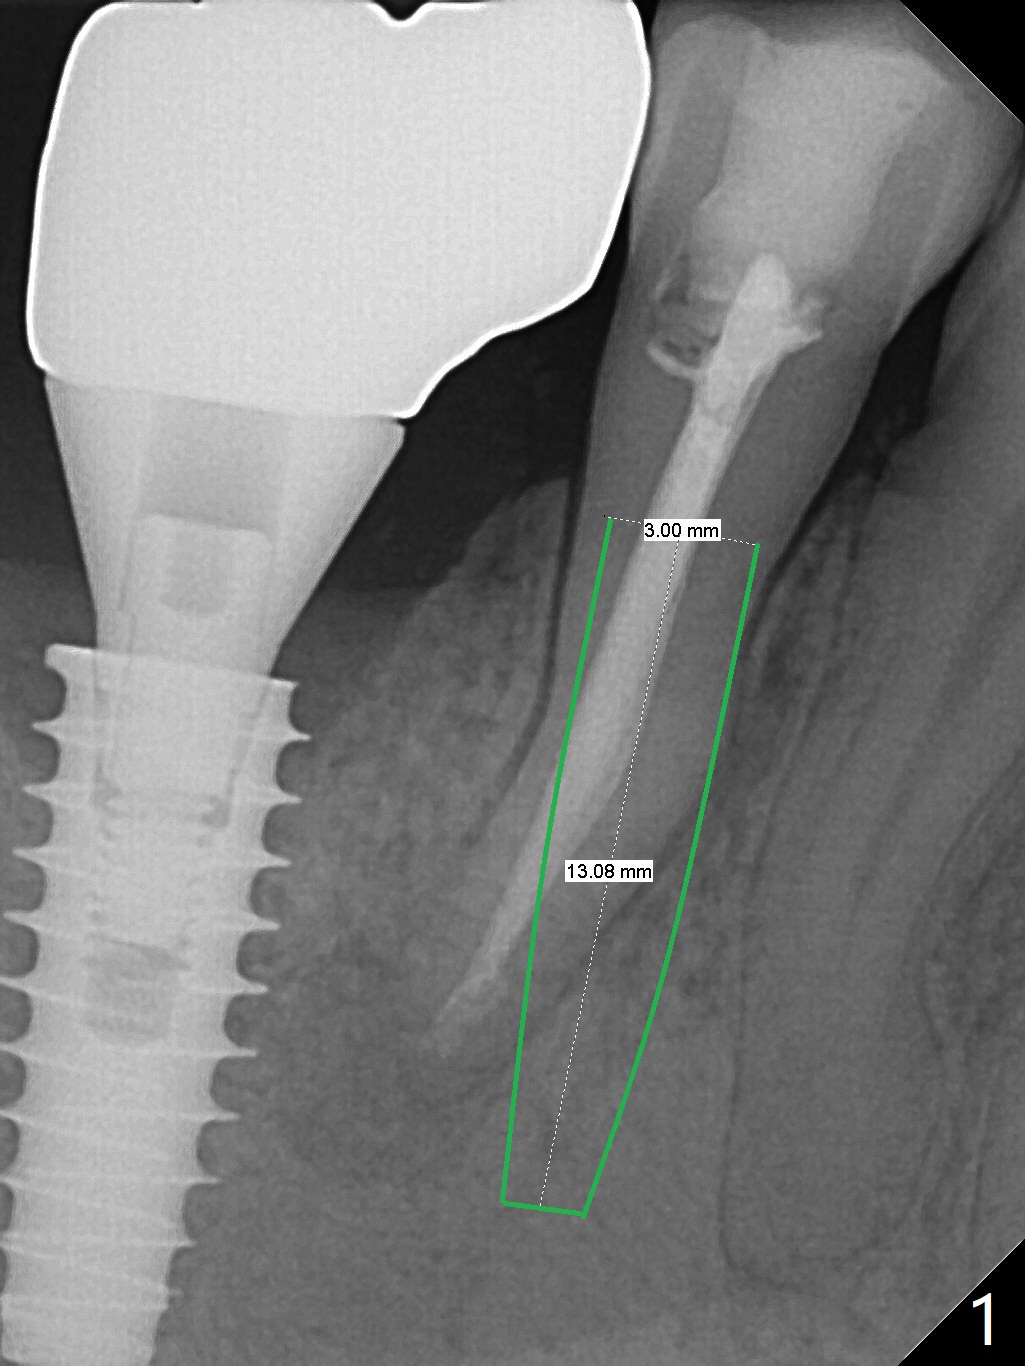

A 48-year-old man has pain 4.5 months post apicoectomy at #29 and requests extraction and immediate implant. Since the mesiodistal bone width is limited, the 1st option is to place a narrow IBS implant (Fig.1). First at all, use 1.6 mm drill to establish osteotomy with correct trajectory. If the effort to change the trajectory and position fails, switch to a 3x14 or 16 1-piece implant to reduce the chance of abutment screw loosening. If intraop PA shows the mesiodistal bone width is not so narrow and stability is not ideal, use a UF implant (Fig.2). CBCT coronal section shows a 15 mm long implant may perforate the lingual plate (Fig.3 L). To place an implant lingually, the coronal end of the lingual plate should be removed (*).